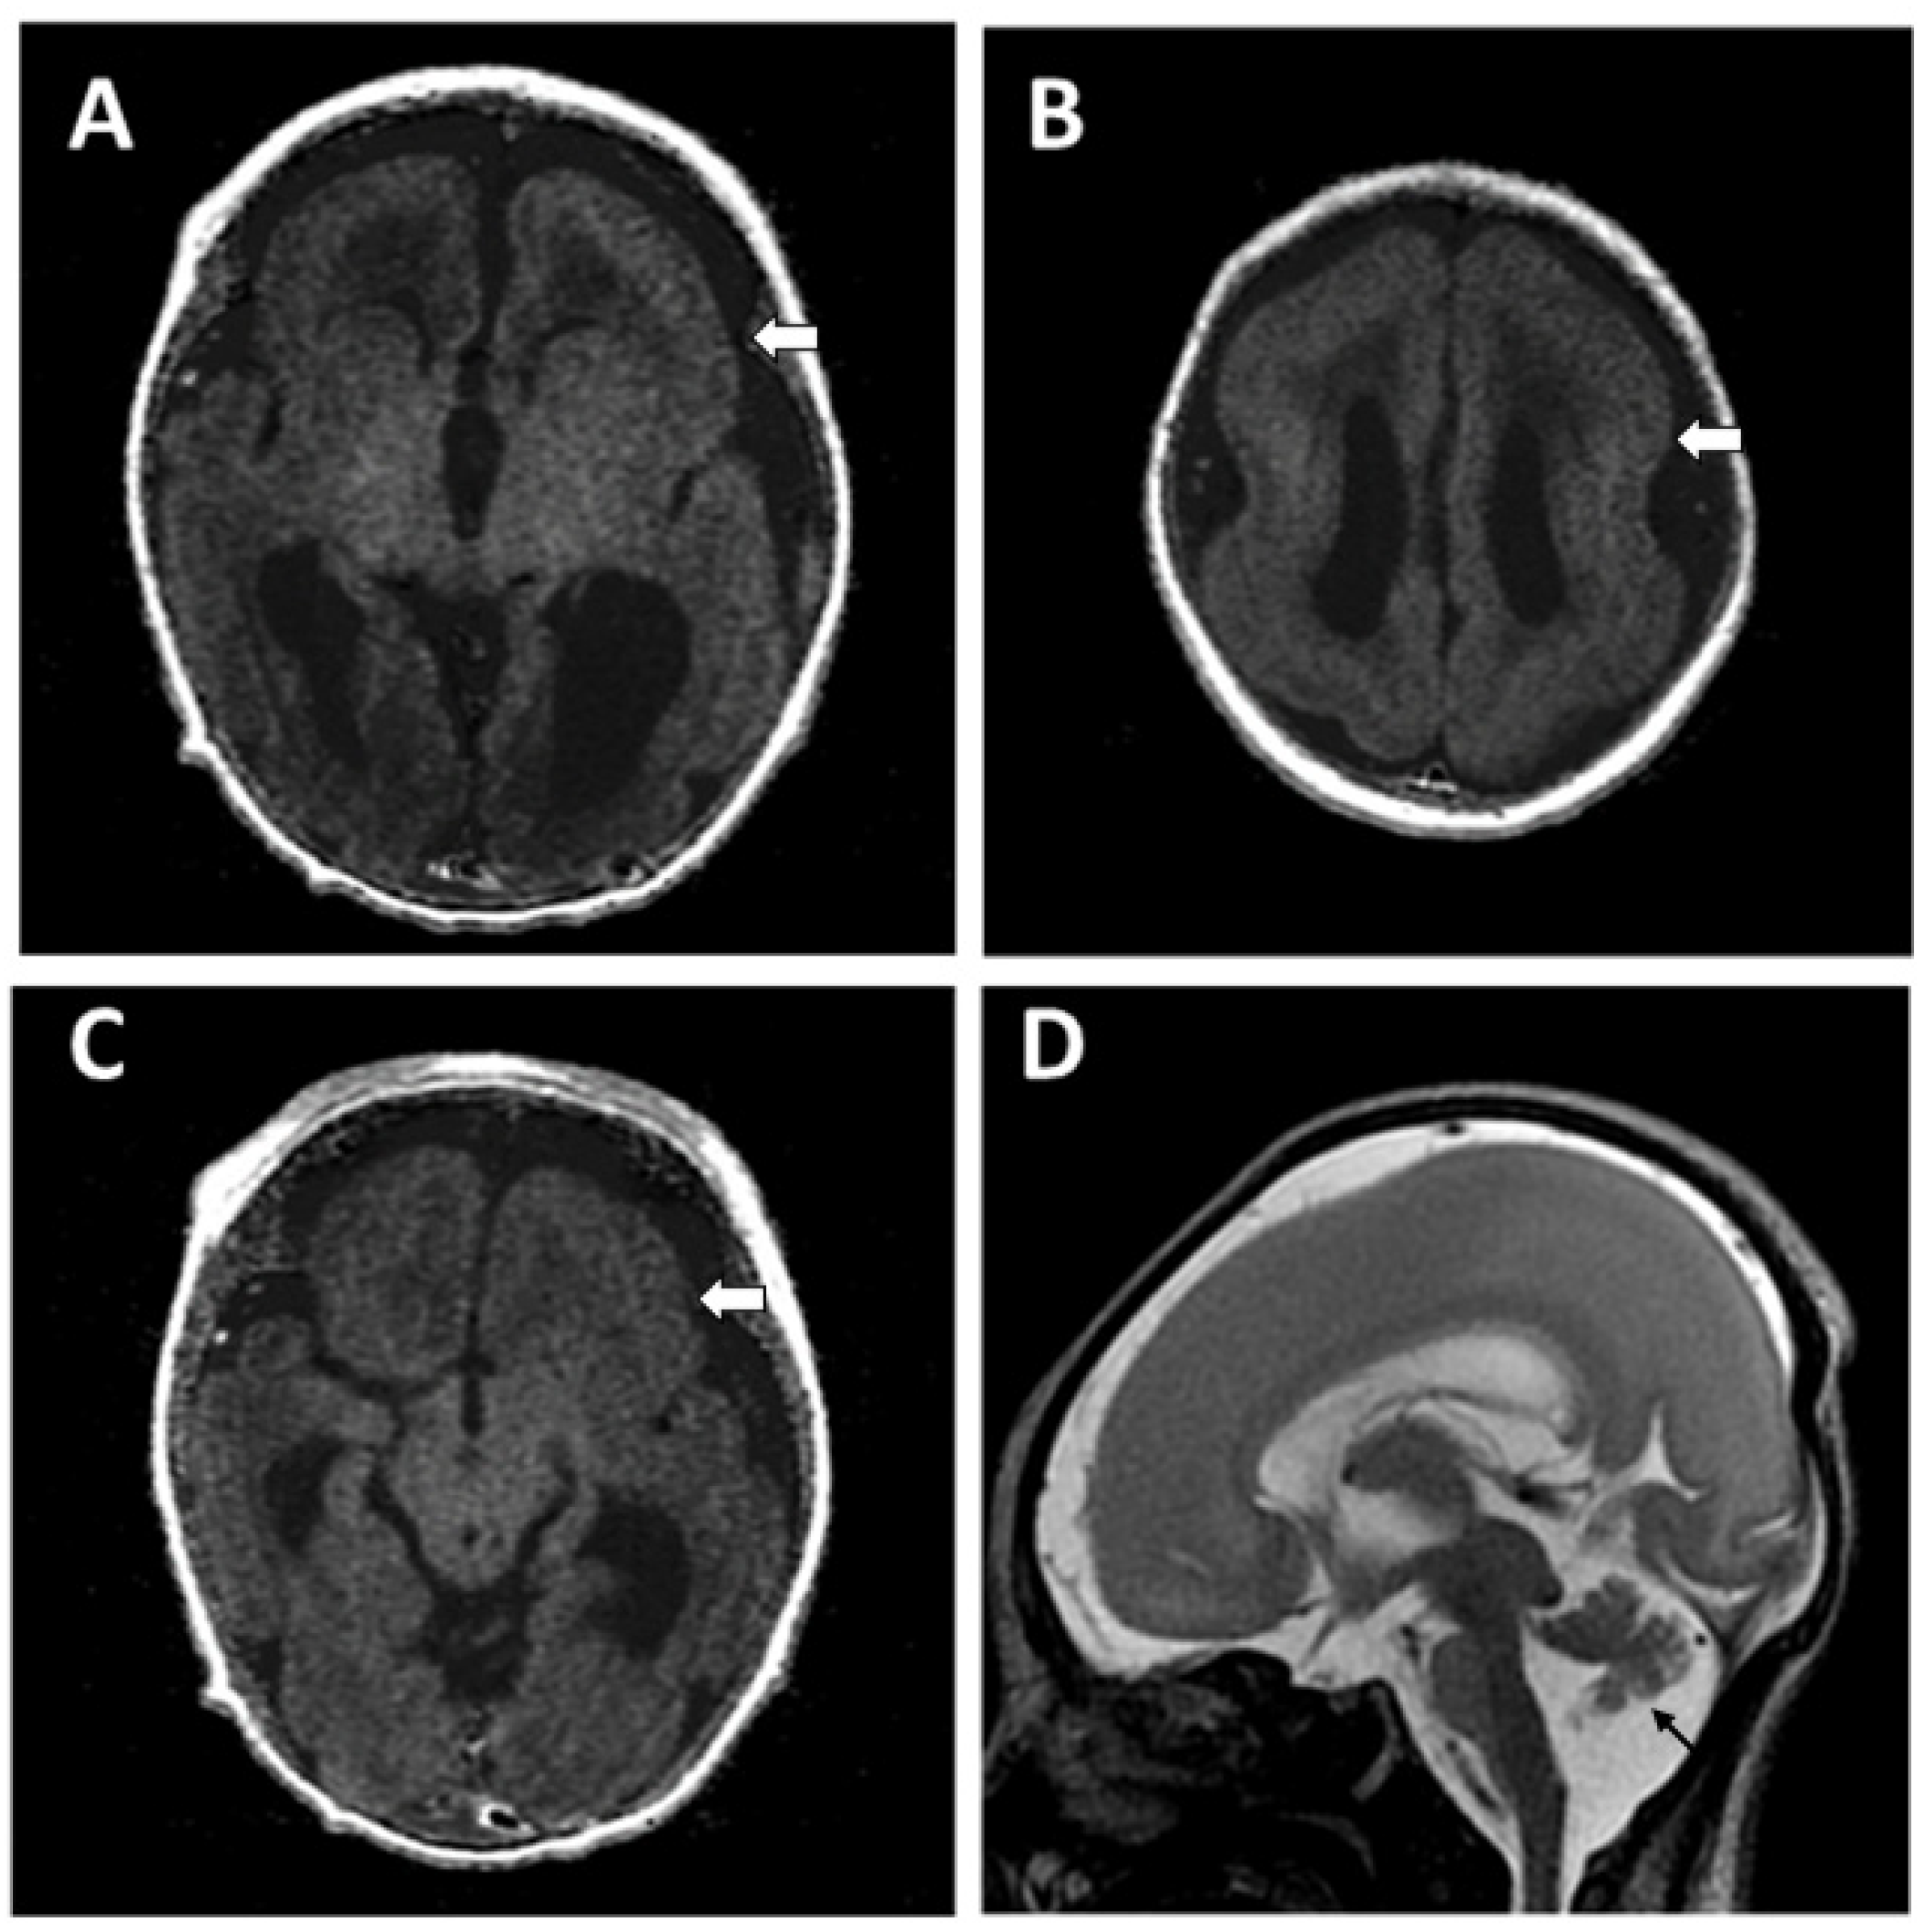

2.2. Case 2

Patient Information